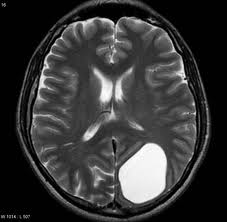

2-This defect may communicate with the ventricle known as open lip schizencephaly or do not communicate known as closed lip schizencephaly.

| Open lip schizencephaly |